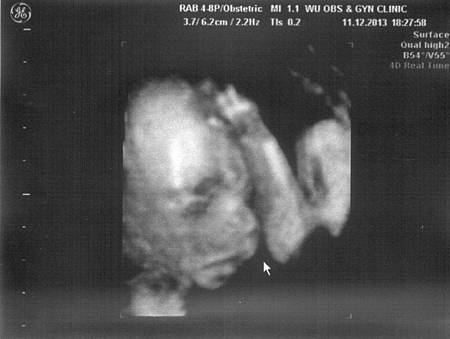

• 21W產檢

21W4D-2

去年(!?)12/11做第五個月的產檢,一切都很順利囉!